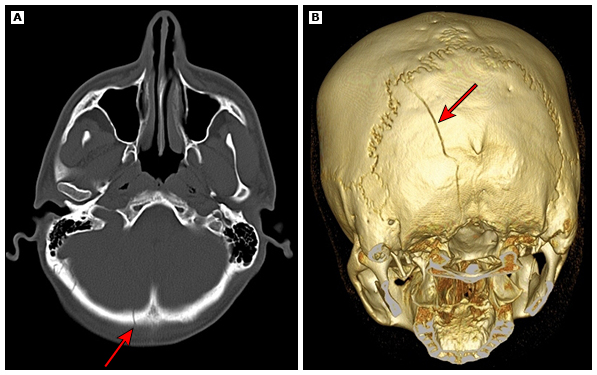

Fratura de Crânio

Linhas radiolucentes com bordas irregulares, podem ser lineares, deprimidas ou cominutivas. Avaliar sempre a presença de ar intracraniano (pneumocefalia) ou sangramento associado.

TC de Órbitas com Reconstrução 3D

Técnica útil para avaliação de fraturas complexas e planejamento cirúrgico. Requer aquisição com cortes finos e reconstruções especiais.

Protocolo Recomendado:

- Aquisição isotrópica (0.5-0.6 mm)

- kV reduzido (100-110) para minimizar dose no cristalino

- Reconstruções em MPR (Multiplanar Reconstruction) e 3D

- Algoritmo de alta resolução para avaliação óssea